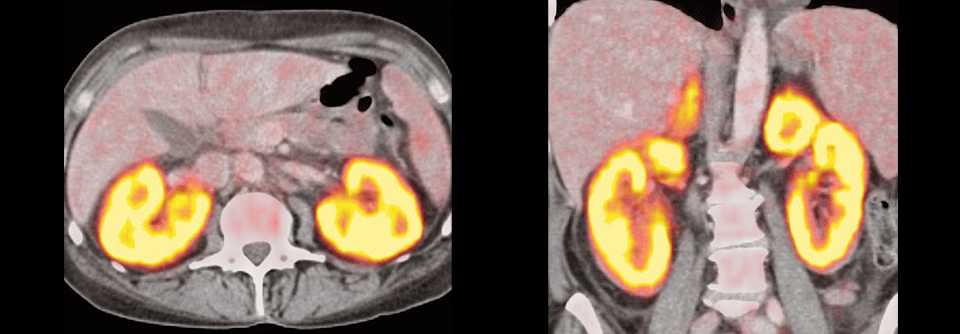

Diffuses großzelliges B-Zell-Lymphom

Beim diffusen großzelligen B-Zell-Lymphom kommen „die Neuen“ zum Einsatz, wenn die initiale R-CHOP(Rituximab, Cyclophosphamid, Doxorubicin, Vincristin , Predniso(lo)n, Prednisolon)-Immunchemotherapie nicht zur Heilung führt. Vor allem die CAR-T-Zellen haben hier laut Professor Dr. Kami Maddocks von der Ohio State University eine…